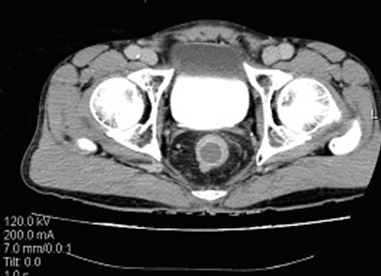

A 71-year-old male patient presented with constipation for one month. No rectal bleeding, pain or tenesmus were associated. Patient did not have a history of contact with or any symptoms of pulmonary tuberculosis. Physical examination was unremarkable, but digital rectal examination revealed hard annular growth about five cm from the anal verge. Colonoscopy showed annular thickening of lower rectum which was covered with a whitish patch. (Figure 1) On suspicision of malignancy, multiple biopsies were taken. Endorectal ultrasonography (B-K Medical HAWK 2102; 2050 anorectal radial probe and a 15 MHz transducer) demonstrated a hypoechoic lesion with pseudopodia. (Figure 2) Computed tomography confirmed a longitudinal circumferential rectal tumor suggestive of malignancy with multiple pelvic lymphadenopathy. (Figure 3) Endoscopic biopsy showed caseous necrosis with inflammatory cells which was suggestive of tuberculosis. (Figure 4) No malignant cells were seen. Chest X-ray showed active pulmonary tuberculosis with positive result for sputum acid fast stain. Anti-HIV ELISA was non-reactive. Serum carcinoembryonic antigen (CEA) was 4 ng/mL. Tissue acid fast stain and tissue culture for tuberculosis were negative. Standard six-month anti-tuberculosis medication was prescribed. The patient responded well to the treatment. His constipation improved. His rectal tumor had receded at the six- month endoscopic follow-up. | ||||||